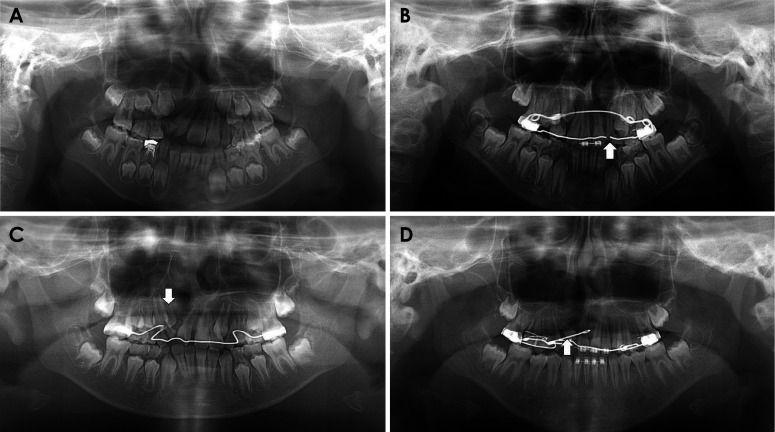

目的:本研究旨在明确有无腭裂的齿槽裂患者的全景图像差异,重点是鼻中隔和鼻底交界处形成的线(上线)的可见度以及上颌侧切牙的外观:对 238 名唇裂患者的全景照片进行分析,以了解上线的可见度(包括清晰、模糊或不可见)以及上颌侧切牙的外观(包括先天缺失、发育不全、萌出延迟和内倾)。结果显示,腭裂患者和非腭裂患者在这些可见度和外观的分布比例上存在差异:结果:腭裂患者和非腭裂患者的上线能见度分布存在明显差异(p):在全景图像中发现了两种差异。首先是腭裂患者的上线消失(不可见),其次是单侧腭裂患者患侧上颌侧切牙的内倾角发生变化。

Purpose: The purpose of this study was to clarify the panoramic image differences of cleft alveolus patients with or without a cleft palate, with emphases on the visibility of the line formed by the junction between the nasal septum and nasal floor (the upper line) and the appearances of the maxillary lateral incisor.

Materials and methods: Panoramic radiographs of 238 patients with cleft alveolus were analyzed for the visibility of the upper line, including clear, obscure or invisible, and the appearances of the maxillary lateral incisor, regarding congenital absence, incomplete growth, delayed eruption and medial inclination. Differences in the distribution ratio of these visibility and appearances were verified between the patients with and without a cleft palate using the chi-square test.

Results: There was a significant difference in the visibility distribution of the upper line between the patients with and without a cleft palate (p<0.05). In most of the patients with a cleft palate, the upper line was not observed. In the unilateral cleft alveolus patients, the medial inclination of the maxillary lateral incisor was more frequently observed in patients with a cleft palate than in patients without a cleft palate.

Conclusion: Two differences were identified in panoramic appearances. The first was the disappearance (invisible appearance) of the upper line in patients with a cleft palate, and the second was a change in the medial inclination on the affected side maxillary lateral incisor in unilateral cleft alveolus patients with a cleft palate.